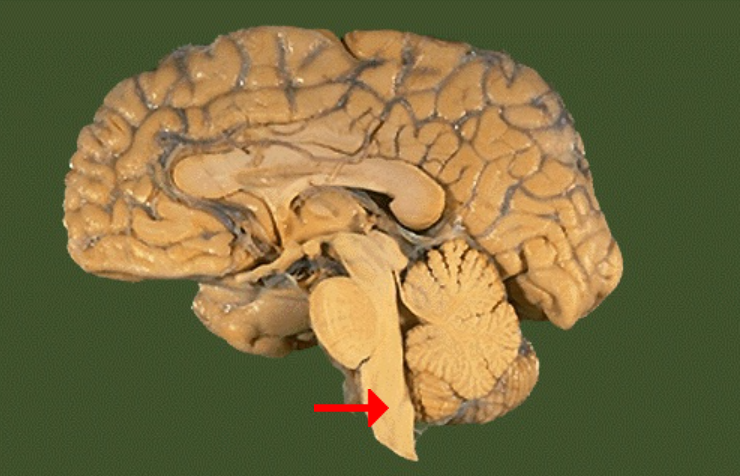

Label this brain part

Frontal lobe

Label this brain part

Parietal lobe

Label this brain part

Occipital lobe

Label this brain part

Thalamus

Label this brain part

Midbrain

Label this brain part

Fourth ventricle

Label this brain part

Medulla

Label this brain part

Corpus callosum

Label this brain part

Mammillary body

Label this brain part

Cerebellum

Label this brain part

Aqueduct of Sylvius

Label this brain part

Tectum (of midbrain)

Label this brain part

Septum pellucidum